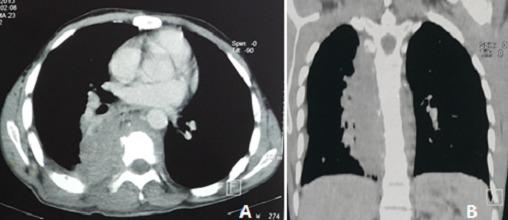

诺卡菌病是一种由诺卡菌属细菌引起的罕见但严重的感染,诺卡菌属属于放线菌目。如果诺卡菌病能够影响免疫功能正常的成年人,那么它通常是影响免疫系统较弱个体的疾病。肺部受累是最常见的表现形式,其正确的治疗基于诊断,但由于症状不具特异性且标本检查结果不明确,诊断往往会延迟。我们在此报告两例免疫功能正常患者的诺卡菌病病例。第一例是一名24岁有吸烟和酗酒史的男性,因胸痛和少量咯血持续两个月入院,伴有背部皮下瘘管性脓肿。影像学评估显示右纵隔-肺组织肿块,伴有相邻肋骨溶解及右侧椎旁组织播散。细菌学采样结果为阴性,于是对病变进行超声引导下活检,确诊为诺卡菌感染。第二例是一名22岁男性,8年前有胸膜结核病史,2011年有结核病复发(纵隔脓肿)。因基于慢性咳嗽、全身状况改变及肝脾肿大怀疑结核病复发而入院。胸部CT扫描显示有肺泡实变伴胸膜炎。住院期间出现了脓性皮下肿胀。脓液细菌学分析确诊为诺卡菌病。诺卡菌菌株对除黏菌素和复方新诺明外的所有抗生素均耐药。本研究旨在突出肺部诺卡菌病的临床和影像学特征,重点关注诊断和治疗方面的困难,尤其是在结核病高发且诺卡菌病发病率极低的国家。